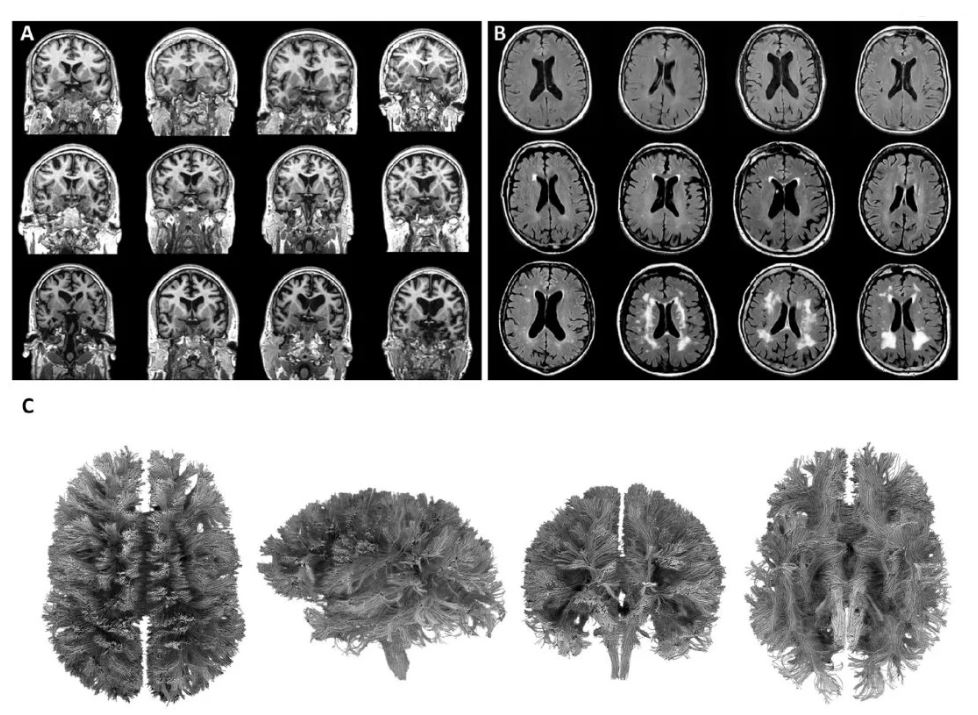

تفاوت در سلامت مغز و نقش تصویربرداری

یکی از جذابترین یافتهها به ساختار و عملکرد مغز مرتبط است. با استفاده از تکنیکهای پیشرفته تصویربرداری، پژوهشگران تفاوتهای قابلتوجهی را در سلامت مغز میان افراد همسن نشان دادند. این یافتهها سؤالات مهمی درباره عوامل مؤثر بر این تفاوتها و امکان تعدیل آنها از طریق تغییرات سبک زندگی مطرح میکند.